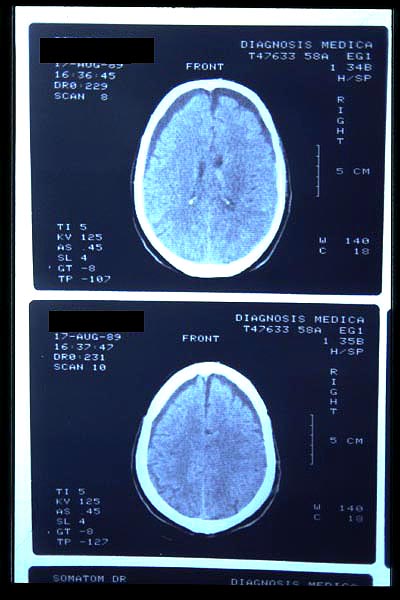

AVC amplio de territorio de A. cerebral media